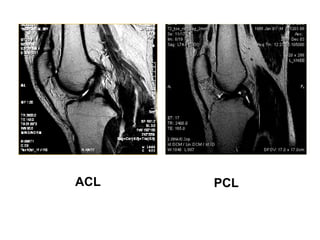

ACL & PCL

ACL PCL